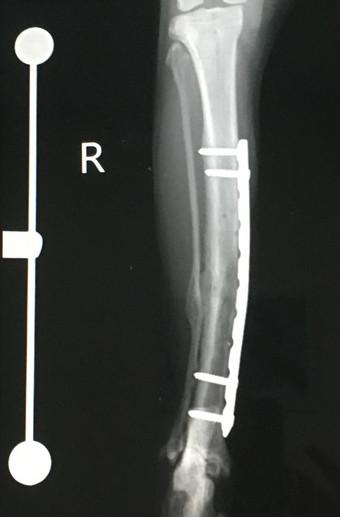

7月17日 手術から 12ヶ月 後

2回目のプレート抜去

メインプレートとボルト4本抜去。

8月21日 手術から 13ヶ月 後

札幌の病院で経過観察、骨形成OKで問題なし。